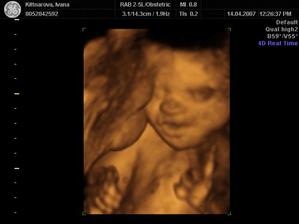

Někdy kolem 12. července by se nám mělo narodit naše první miminko. Všichni se už moc těšíme :o)

Podle ultrazvuku ve 20.tt by to měl být chlapeček.